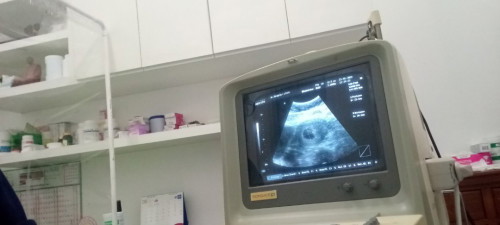

เจอแต่ถุงตั้งครรภ์

ขอสอบถามหน่อยค่ะไปอัลตร้าซาวด์มาเมื่อวานหมอบอกเหนแต่ถุงตั้งครรภ์ ยังไม่เหนตัวอ่อน มีโอกาสท้องลมสูงไหมค่ะอายุครรภ์ 8w#ขอบคุณล่วงหน้านะคะ

มีโอกาสท้องลมอยู่คะ บ้านนี้ก็ซาวด์ตอน8wเจอแค่ถุงตั้งครรภ์หมอนัดซาวด์อีกที10wพอดีมีอาการปวดท้องแบบบีบๆมากก่อนวันนัดหมอเลยซาวด์ใหม่ก็ยังไม่เจอตัวเด็กเขาเลยส่งไปขูดมดลูกอีกรพ.หนึ่งบอกเราว่าท้องลมพอไปถึงรพ.ที่2หมอตรวจซ้ำใหม่หลายรอบหมอบอกเจอถุงไข่แดง+ถึงตั้งครรภ์มีโอกาสที่น้องจะโตหมอให้โอกาสอีก2อาทิตย์ถ้าไม่เจอจริงๆได้ขูดมดลูกคะ